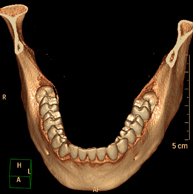

Prova radiològica que consisteix en obtenir imatges de la oïda d'alta definició anatòmica, (conducte auditiu intern i extern, timpà, ossets de l'oïda) mitjançant l'ús d'un equip de TC (Tomografia Computeritzada). Indicacions: trastorns de l'audició, quadres vertiginosos, mareigs, acúfens (xiulets). - TC Dental

Prova radiològica que consisteix en obtenir imatges dels ossos maxil·lars d'alta definició anatòmica (peces dentals, trajecte del nervi dentari), mitjançant l'ús d'un equip de TC (Tomografia Computeritzada). Indicacions: estudi previ a l'extracció dental, estudi previ als implants, tumors, abscés. - TC Sins paranasals